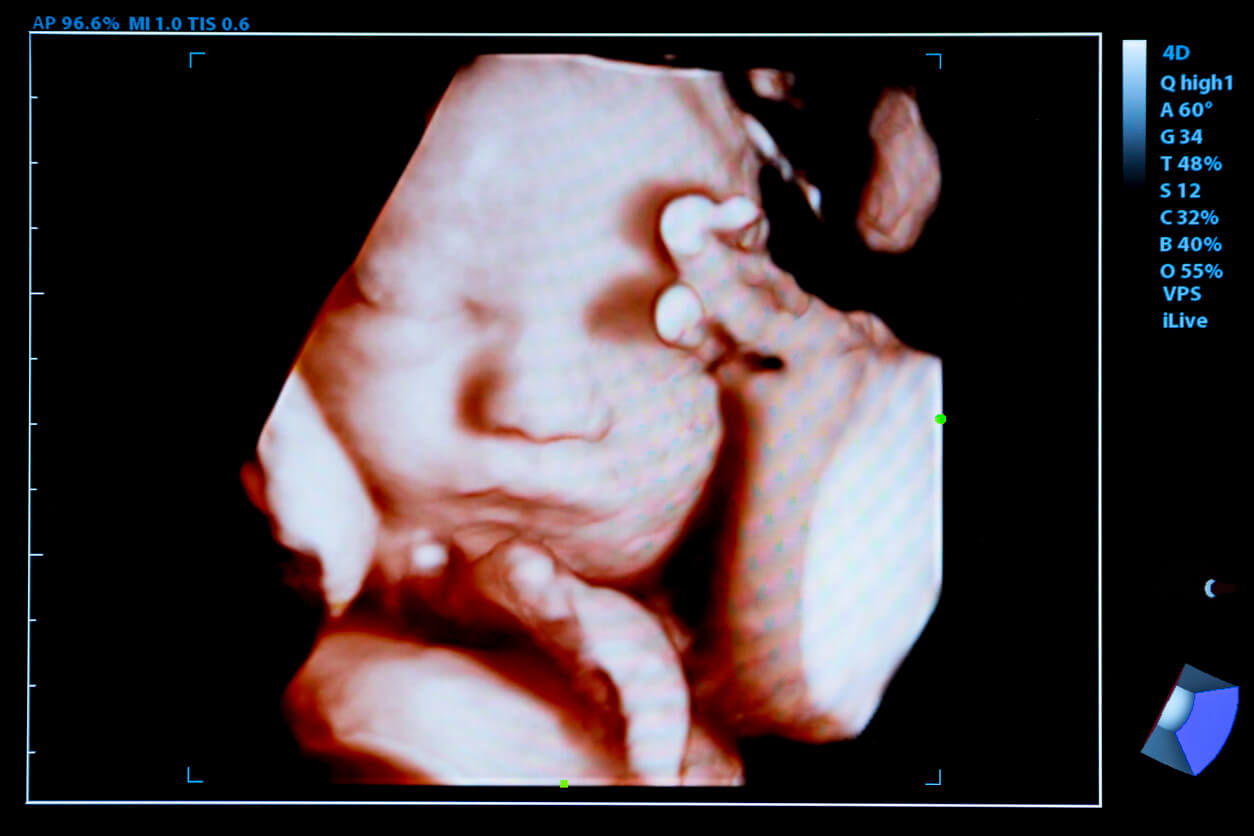

A Living Will is a legal document that outlines your end of life medical wishes Make yours for free and save print download Ultrassom 4D O Que E Quando Fazer Sou Mam e

Understanding 2D 3D And 4D Pregnancy Ultrasounds International

Cherished Memories 3D 4D Ultrasound 40 Photos Ultrasound Imaging

Ultrassom 4D O Que E Quando Fazer Sou Mam e